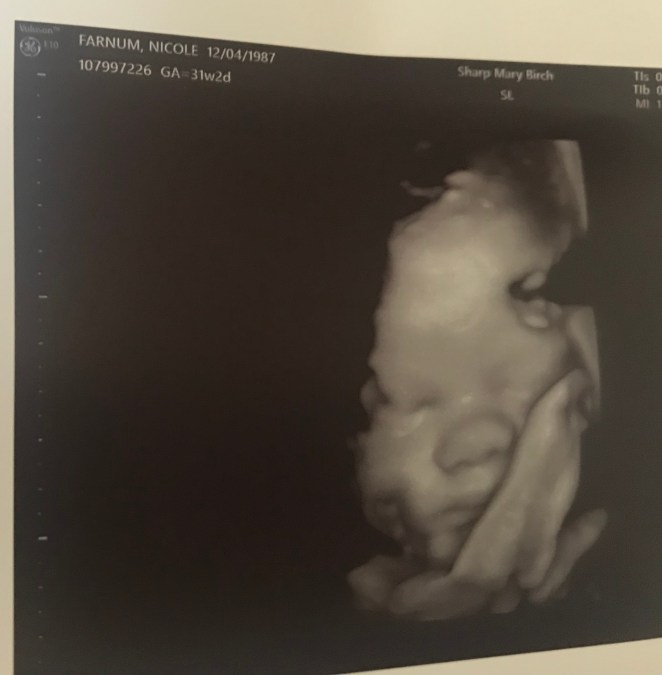

In here I am monitored every 8 hours, have blood draws every 3 days, have an IV that has to be flushed frequently, get visits from doctors, nurses, social workers, etc. and get weekly ultrasounds. Nora hates being on the monitor and kicks it off, so she has become known as the wild baby on the floor. Not sure where she gets that stubbornness… 😬😉🤷♀️ I love ultrasound days because we get a glimpse of her precious face, if she allows it. Often times she turns her back or covers her face. I think we have a sassy little girl on our hands, but I’ll take it.

Today we had an ultrasound and got some exciting news! Nora is measuring at 4 lbs 13 oz. and a week ahead of schedule. Along with this the doctor caught her drinking amniotic fluid and breathing well on the scan. She explained that both of these things are great signs since she will be taken by c-section early. After my scan I got a call and they have set our c-section date for Monday June 17th! That means that our sweet girl will be here in 17 days! 😭 The doctor also confirmed she suspects that a hysterectomy will be necessary following my c-section to avoid major issues with me. We are mentally preparing for this.